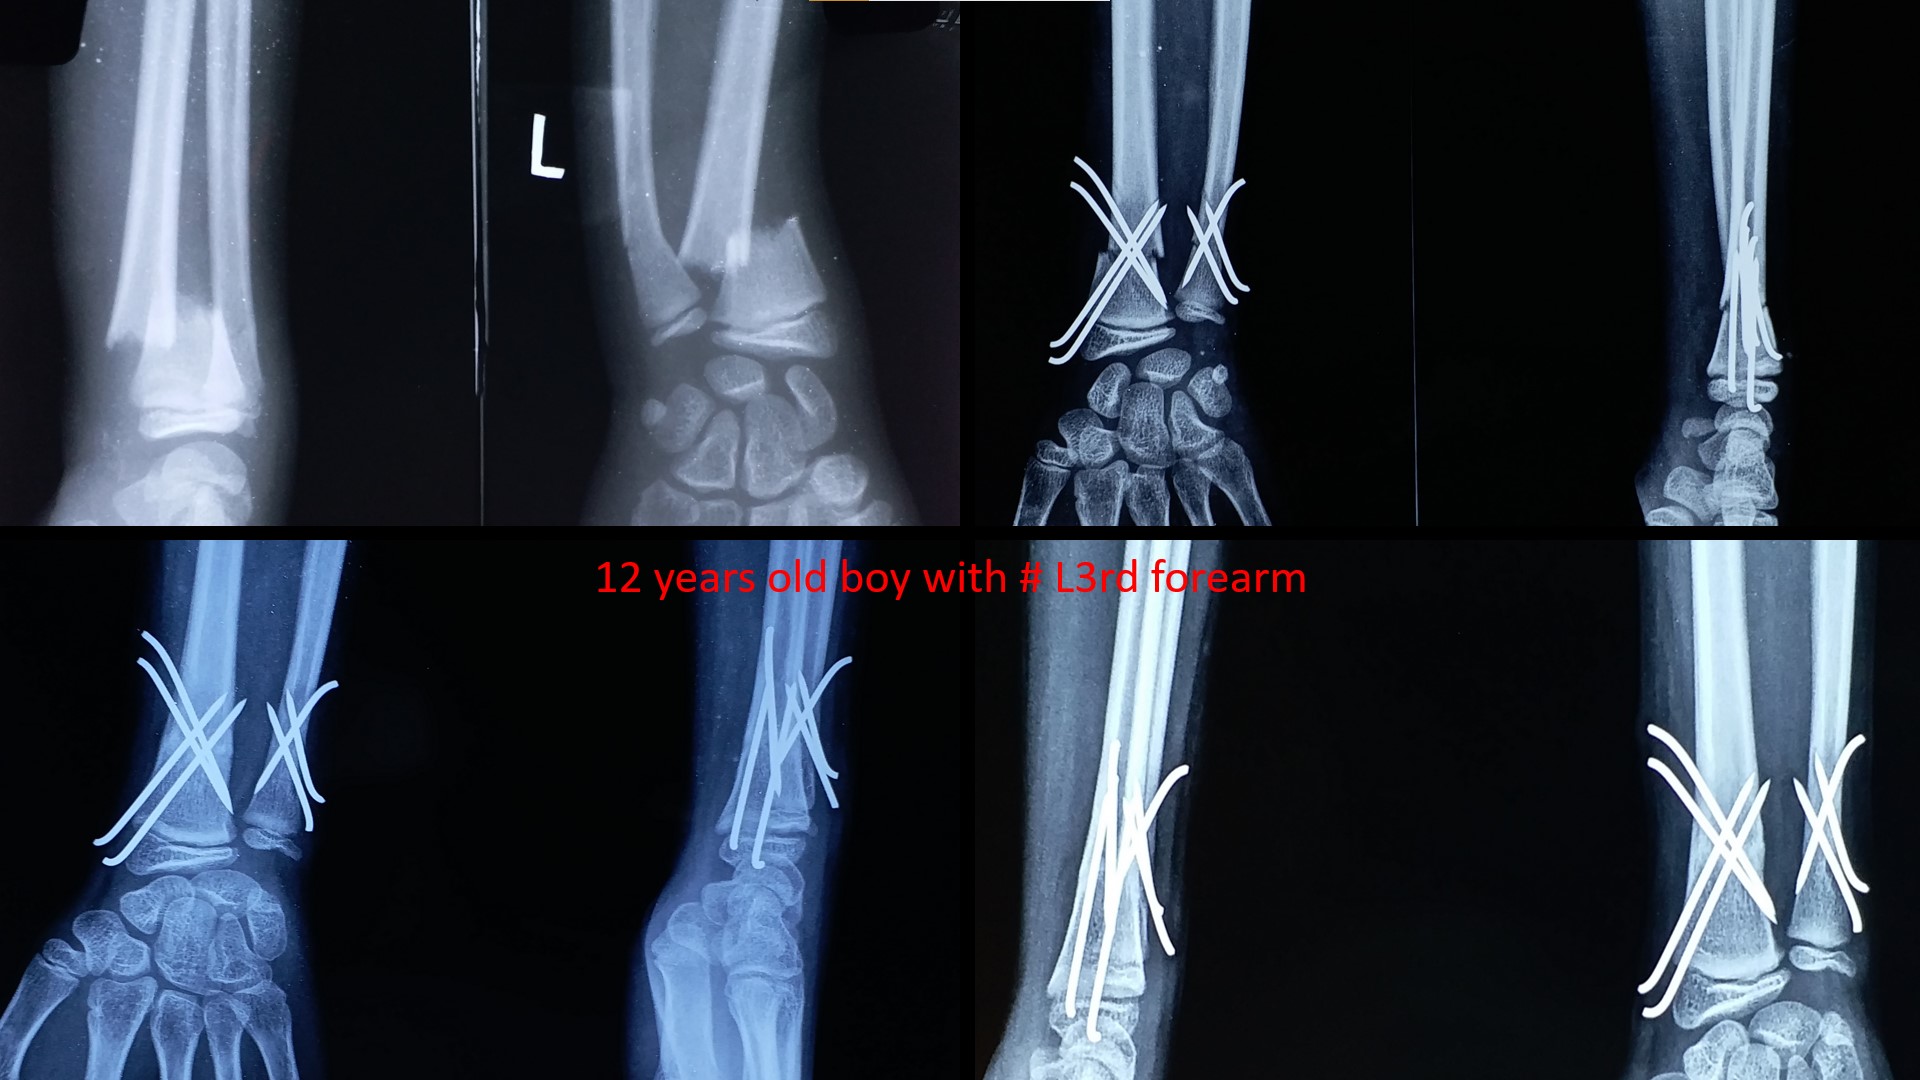

FRACTURE LOWER 3RD FOREARM